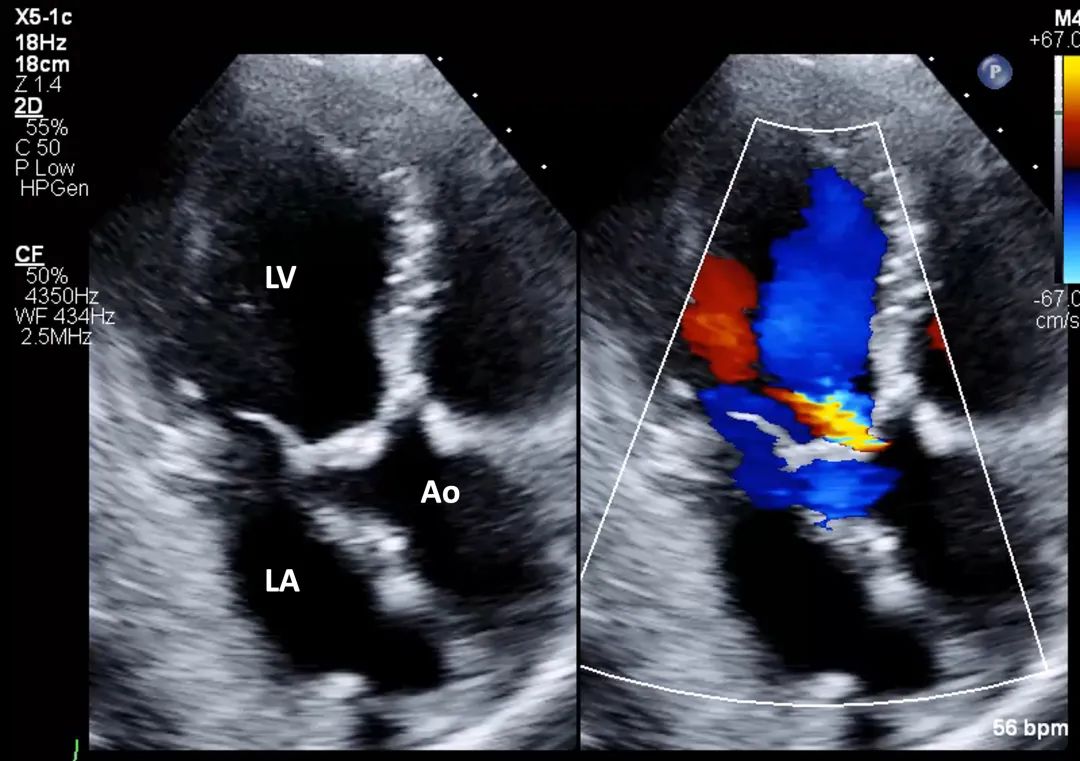

7、心尖五腔心切面: 在主动脉瓣处的彩色多普勒显示主动脉瓣狭窄引起的彩色镶嵌血流(mosaic color flow)模式,且可显示主动脉瓣反流(aortic regurgitation,AR)。应确认湍流起始位置,确保湍流源自瓣膜层面,而非瓣下(如主动脉瓣下隔膜或肥厚型心肌病所致左室流出道梗阻)或瓣上位置(图8,视频5)。

图8. 心尖五腔心切面评价主动脉瓣狭窄(有和彩色多普勒对比)

心尖五腔心切面结合主动脉瓣处彩色多普勒,用于评估流出道梗阻所致狭窄性彩色镶嵌血流模式以及主动脉瓣反流。缩写同图2。

视频5. 心尖五腔心切面应用彩色多普勒(彩色与二维灰阶对比模式),评估主动脉瓣是否存在流出道梗阻所致的狭窄性彩色镶嵌血流模式,以及主动脉瓣反流情况。